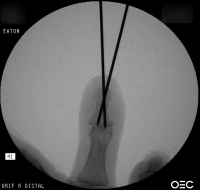

Case 3

Acute mallet fracture treated with percutaneous

pinning: proximal pin stabilizes the fracture

fragment, longitudinal pin maintains distal phalanx

position. |

| Thermoplastic bonding of the protruding ends: appearance at one month. |

| Late result. |